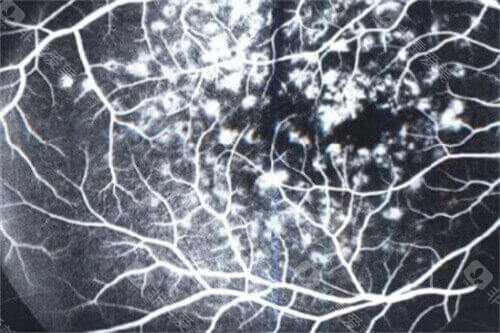

十堰市人民医院眼科中心是湖北激光懂得眼底病影像学组·十堰市眼底病影像诊疗基地,同时还是辽宁锦州医学大学和湖北医药学院眼科学硕士研究生培养点。

余锦强医师是玻璃体视网膜疾病领域的显要,尤其擅长复杂性视网膜脱离、糖尿病视网膜病变的小创口玻切手术,手术精细度高,视功能重建改善显著。华远锋副高医师则在眼外伤急诊处理方面技术娴熟,能够及时救治眼球破裂伤等急症,更大限度保留患者眼球结构和功能。